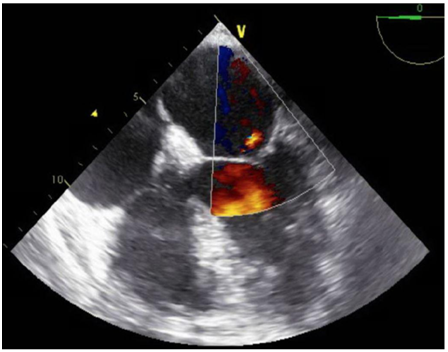

A 47-year-old immunocompetent male with a medical history significant for active intravenous heroin abuse presented to the hospital with fever and respiratory distress. On admission, he was diaphoretic, febrile, and hypoxemic with an oxygen saturation of 70% on ambient air, necessitating intubation and mechanical ventilation. Chest radiography revealed a right lower lobe infiltrate concerning for pneumonia, blood cultures were obtained, and vancomycin and piperacillin-tazobactam were empirically administered. Within 48hours, blood cultures grew Candida tropicalis, and antifungal therapy with micafungin was initiated. Computed tomographic scan of the chest revealed bilateral upper lobe infiltrates and dense consolidations with air bronchograms in the bilateral posterior lobes. Transthoracic echocardiography demonstrated severe aortic thickening and aortic regurgitation but no clear evidence of vegetation despite clinical suspicion for endocarditis. Sites of metastatic infection, including endophthalmitis and septic emboli to the brain were ruled out, and antifungal therapy was adjusted to amphotericin B and flucytosine. A subsequent transesophageal echocardiogram revealed a 1.3cm aortic valve vegetation associated with severe aortic regurgitation, for which he underwent aortic valve replacement with a bioprosthetic pericardial valve. Intra-operative cultures from the aortic valve confirmed Candida Tropicalis. He was discharged to a skilled nursing facility to complete 6weeks of antifungal therapy.

Figure 1 Transesophageal Echocardiogram showing a 1.3 cm vegetation in right coronary cusp.